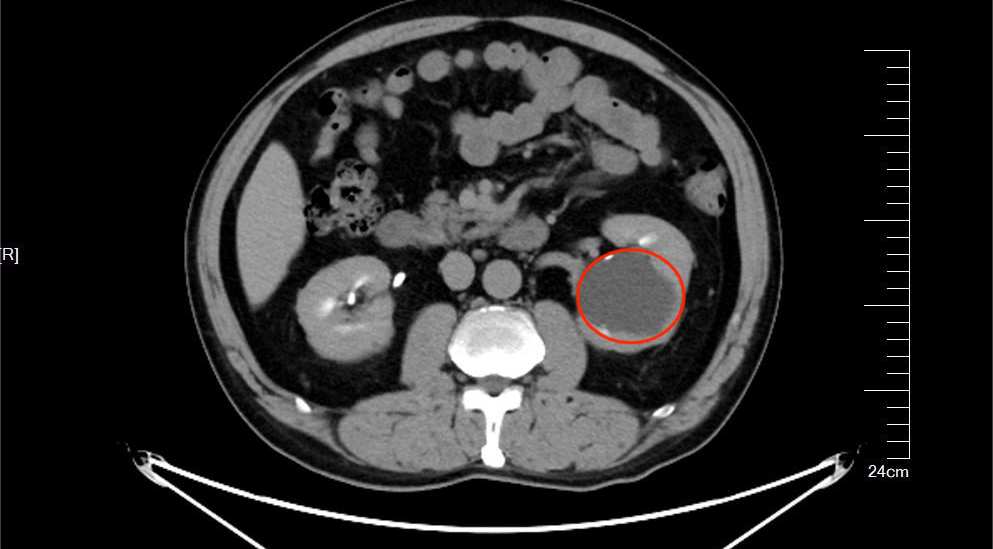

家住宿州的刘先生(化名)五年前体检时查出左肾患有囊肿,随着时间的流逝,这几年他的囊肿越长越大,开始出现腹部疼痛的问题。他急忙赶到皖北煤电集团总医院(以下简称“皖北总院”)泌尿外科就诊。

明确刘先生目前囊肿的位置和大小,并进行详细的综合评估,最终决定为患者实施左输尿管软镜下钬激光肾盂囊肿开窗术。

“肾盂旁囊肿位置特殊,紧邻肾脏集合系统和重要血管,传统腹腔镜手术容易损伤周围结构,风险较高。”郭主任介绍道“现在我们决定为刘先生实施左输尿管软镜下钬激光肾盂囊肿开窗术,是利用人体自然腔道,将一根极细的软镜经尿道、膀胱逆流而上进入输尿管和肾脏,再以钬激光精准切开囊肿壁,实现内引流,相当于在囊肿和肾盂之间‘搭一座桥’。这就像‘倒着走迷宫’,全程没有切口,近乎零出血。”